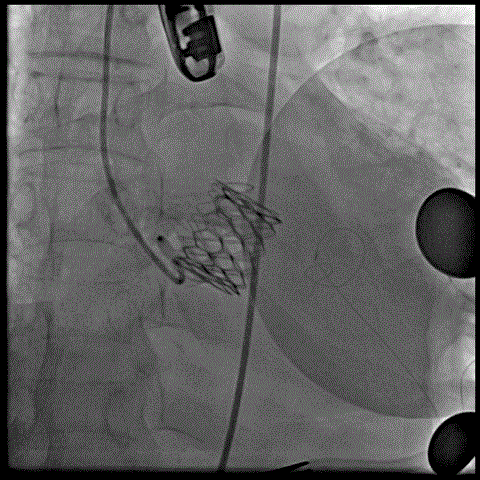

术前经详尽评估患者病情,通过CT重建观察到既往植入的自膨式TAVR瓣膜呈椭圆形,测量瓣环直径,及双侧冠脉开口高度,并评估外周血管入路。由于患者外周血管钙化严重且迂曲,经外周血管途径有较大风险,决定对该病例采用经心尖途径行TAVR瓣膜内 “瓣中瓣”手术。但第二次经心尖途径又将面临心脏、肺、胸壁肌肉组织的粘连,手术难度大。经术前反复讨论和仔细测量毁损TAVR瓣膜的平均内径和冠脉开口高度,决定选用25号 Renato球扩瓣膜。Renato球扩式瓣中瓣可以提供更强的径向支撑力,瓣架高度低,术前模拟植入评估显示冠脉梗阻风险低。手术过程顺利,最终瓣中瓣植入位置理想,功能表现出色,主动脉根部造影及经食道超声观察无瓣中及瓣周反流。

球扩瓣中瓣瓣 中瓣植入后主动脉根部造影